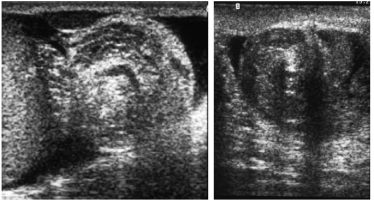

A. Dans sa forme typique serrée (figure 28.1)

- Visualisation de la spire de torsion en région inguinale (« whirlpool sign » ou signe du tourbillon ou spirale vasculaire, qui correspond à l’enroulement des vaisseaux spermatiques). La spécificité et la sensibilité de ce signe sont très élevées. L’hypervascularisation du cordon est variable.

- Testicule ascensionné avec modification de l’orientation de son grand axe ; échostructure hétérogène, hypoéchogène.

- Absence de flux intratesticulaire et épididymaire en cas de forme très serrée.

- Diminution de la vascularisation intratesticulaire en doppler couleur avec chute de la vitesse en doppler pulsé par rapport au côté controlatéral en cas de torsion serrée ou peu serrée.

Fig. 28.1. Échographie, plan sagittal.

Orifice profond du canal inguinal, spire de torsion (whirlpool sign). Ces clichés proviennent de deux patients différents.

Source : CERF, CNEBMN, 2022.